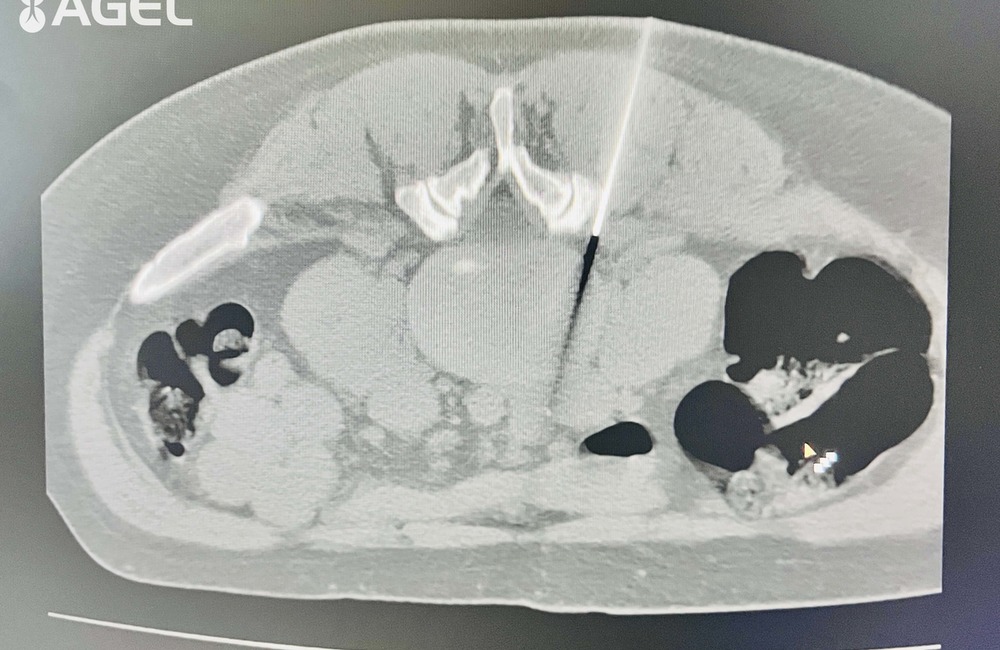

FOTO: CT pracovisko bánovskej nemocnice začalo s poskytovaním ozónoterapie

FOTO: CT pracovisko bánovskej nemocnice začalo s poskytovaním ozónoterapie, foto 1

Zdroj: Nemocnica AGEL Bánovce